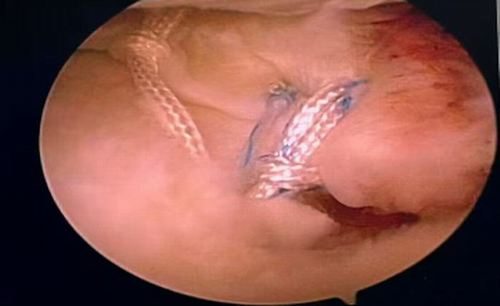

患者,汪某,因“膝关节疼痛”前往奉节县中医院就诊,磁共振检查提示“左膝关节内侧半月板后根撕裂‘’,完善术前准备,与患者详细沟通治疗方案后,于2月10日在全麻下行关节镜手术,术中发现左膝内侧半月板后根部撕裂,术中给予后根部止点重建,术后探查半月板根部稳定,手术非常顺利,患者十分满意,已康复出院。

术后